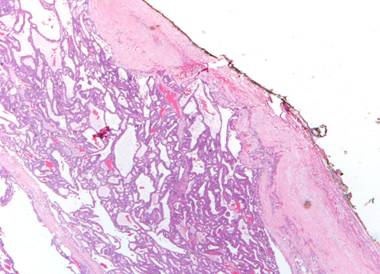

Il carcinoma acinico può avere una pseudocapsula, frequentemente incompleta all'esame

istologico, come si osserva nell immagine seguente.